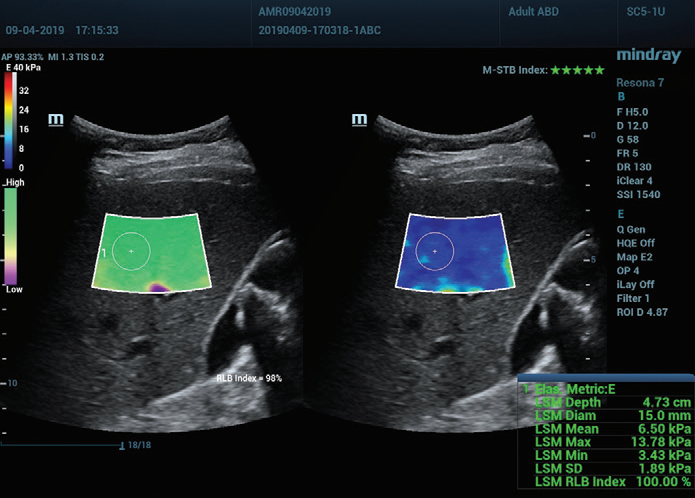

Şekil 1 (devamı): (e) 2D SWE (STE; Mindray, Shenzhen, Çin) ile elde edilen görüntüler. İki kalite kriteri sağlanmıştır: Yıldızlarla gösterilen (en yüksek kararlılık beş yeşil yıldızla gösterilmiştir) hareket kararlılığı (M-STB) endeksi ve mordan yeşile giden (İkincisi en yüksek güvenilirliği gösterir.) güvenilirlik (RLB) haritası. Yıldızlar, edinim sırasında hareketin bir göstergesidir. Dört yıldızdan az olduğunda, edinim sırasında önemli hareket vardır ve bu çerçeve karaciğer sertliği ölçümü için kullanılmamalıdır. (f) Elde edilen görüntüler

Ayrıca Mindray'in Sound Touch Elastography (STE) teknolojisi, 2D Shearvawe elastografi ile elde edilen ölçümler için hareket kararlılığı (M-STB) indeksi, güvenilirlik (RLB) haritası, güvenilirlik (RLB) indeksi vb. ile operatörlerin görüntü elde etme standartlarını onaylamasına yardımcı olan güçlü kalite veya güven faktörleri sağlar.

M-STB indeksi, hareket girişimini ortadan kaldırmaya yardımcı olan hastanın nefesi veya operatörün kompresyonunun neden olduğu doku hareketinin stabilitesini gösterir. Yıldızlarla gösterilir (en yüksek kararlılık beş yeşil yıldızla gösterilir). Güvenilir bir görüntünün ≧4 yeşil yıldıza sahip olması gerekir.

RLB haritası, mordan yeşile giden STE görüntülerinin güvenilirliğini gösterir. İkincisi en yüksek güvenilirliği belirtir. RLB Endeksi ≧%90 olduğunda, görüntü güvenilirdir.